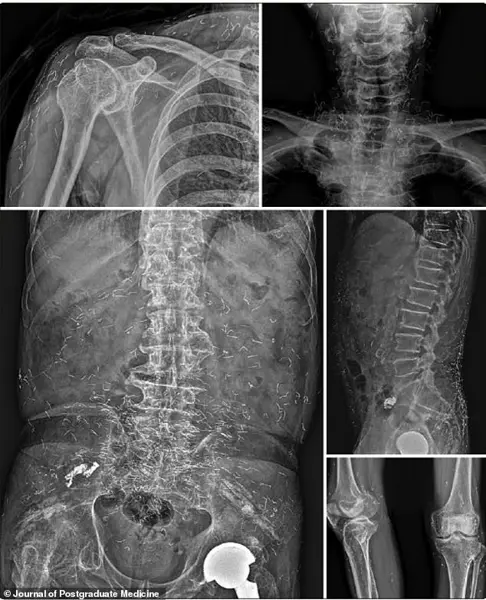

Kim Soo-jin, a surgeon involved in the case. "They can travel through the bloodstream, settle in unexpected places, and create a breeding ground for bacteria." In 2022, a 73-year-old Korean man was hospitalized for a stroke.

During his evaluation, he described a 30-year history of widespread joint pain he had self-treated with gold thread acupuncture.

X-rays revealed thousands of the embedded threads throughout his body. "It was astonishing," said Dr.

Park. "He had no idea that these threads were still inside him, let alone that they could contribute to a stroke." The man had never been diagnosed with rheumatoid arthritis, a chronic disease in which the body’s own immune system attacks healthy joint tissues.

Instead of seeking medical care, he had relied on gold thread acupuncture for years without success.